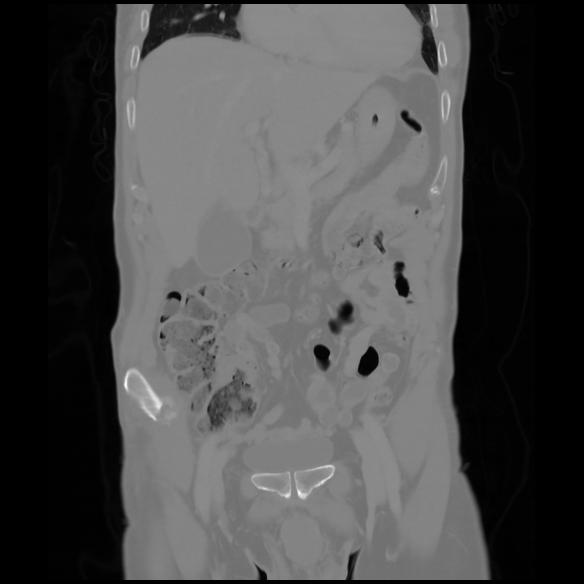

6 CUERPO,CE,Coronal,3.000,CUERPO,Coronal,